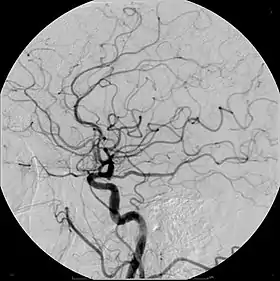

| Cerebral Angiogram obtained using an iodine based contrast medium | |

Due to positive remodeling the plaque build-up shown on angiogram may appear further downstream on the x-ray where the luminal diameter would look normal even though there is severe narrowing at the real site. Because angiograms require x-rays to be visualized the number of times an individual can have it done over a year is limited by the guidelines for the amount of radiation they can be exposed to in a one-year period.[2]